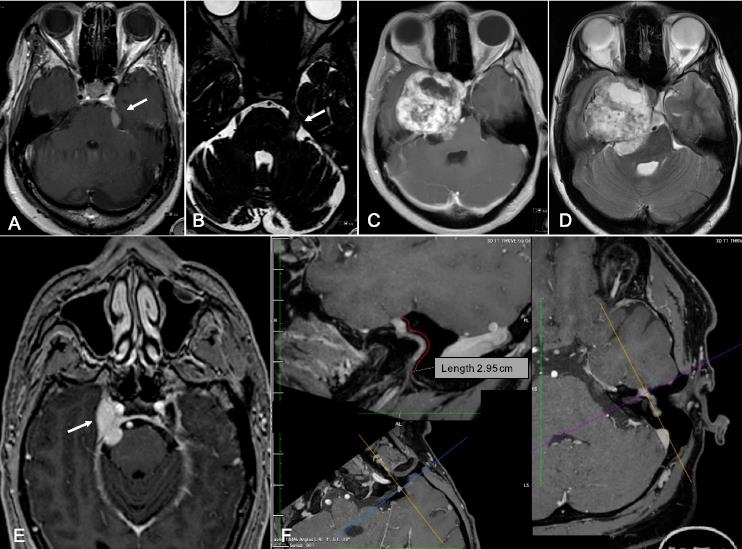

需要詳細(xì)的影像來計(jì)劃對(duì)這些腫瘤的適當(dāng)治療,如果選擇手術(shù),則需要選擇適當(dāng)?shù)氖中g(shù)方法。在Al-Mefty等的一項(xiàng)研究中,大約三分之一的患者在CT成像上顯示骨質(zhì)侵蝕。三叉神經(jīng)鞘瘤對(duì)比均勻增強(qiáng)。它們?cè)贛RI上的表現(xiàn)或是T1加權(quán)低信號(hào)或等信號(hào),或是T2加權(quán)高信號(hào)(圖1)。它們的囊性成分在T2成像上較容易被發(fā)現(xiàn),這是很常見的。更復(fù)雜的序列可以幫助識(shí)別三叉神經(jīng)鞘瘤和鄰近的顱神經(jīng)。薄層T2加權(quán)三維CISS序列在顯示顱神經(jīng)的腦池段時(shí)特別有用。

圖1.T1MRI(A,C,E)和T2MRI加權(quán)(B,D)序列上的三叉神經(jīng)鞘瘤。在T1MRI三個(gè)不同平面上顯示面神經(jīng)鞘瘤(F)。

由于這些腫瘤可能出現(xiàn)在神經(jīng)的任何部位,因此需同時(shí)獲得CT和增強(qiáng)MRI圖像。現(xiàn)代細(xì)致分層的CT成像提供了顳骨的詳細(xì)解剖。面神經(jīng)神經(jīng)鞘瘤通常不表現(xiàn)出骨性“侵蝕”,但被發(fā)現(xiàn)“呈扇貝樣(scallop)”和骨的重塑(remodelthebone),這是符合良性的緩慢生長(zhǎng)的腫瘤。面神經(jīng)神經(jīng)鞘瘤用釓劑(gadolinium)后明顯增強(qiáng)(avidlyenhance)。在T2圖像上,它們?cè)赥1上是高信號(hào)和低信號(hào)到等信號(hào)(圖1)。CISS或3DFIESTA序列可能是有用的。